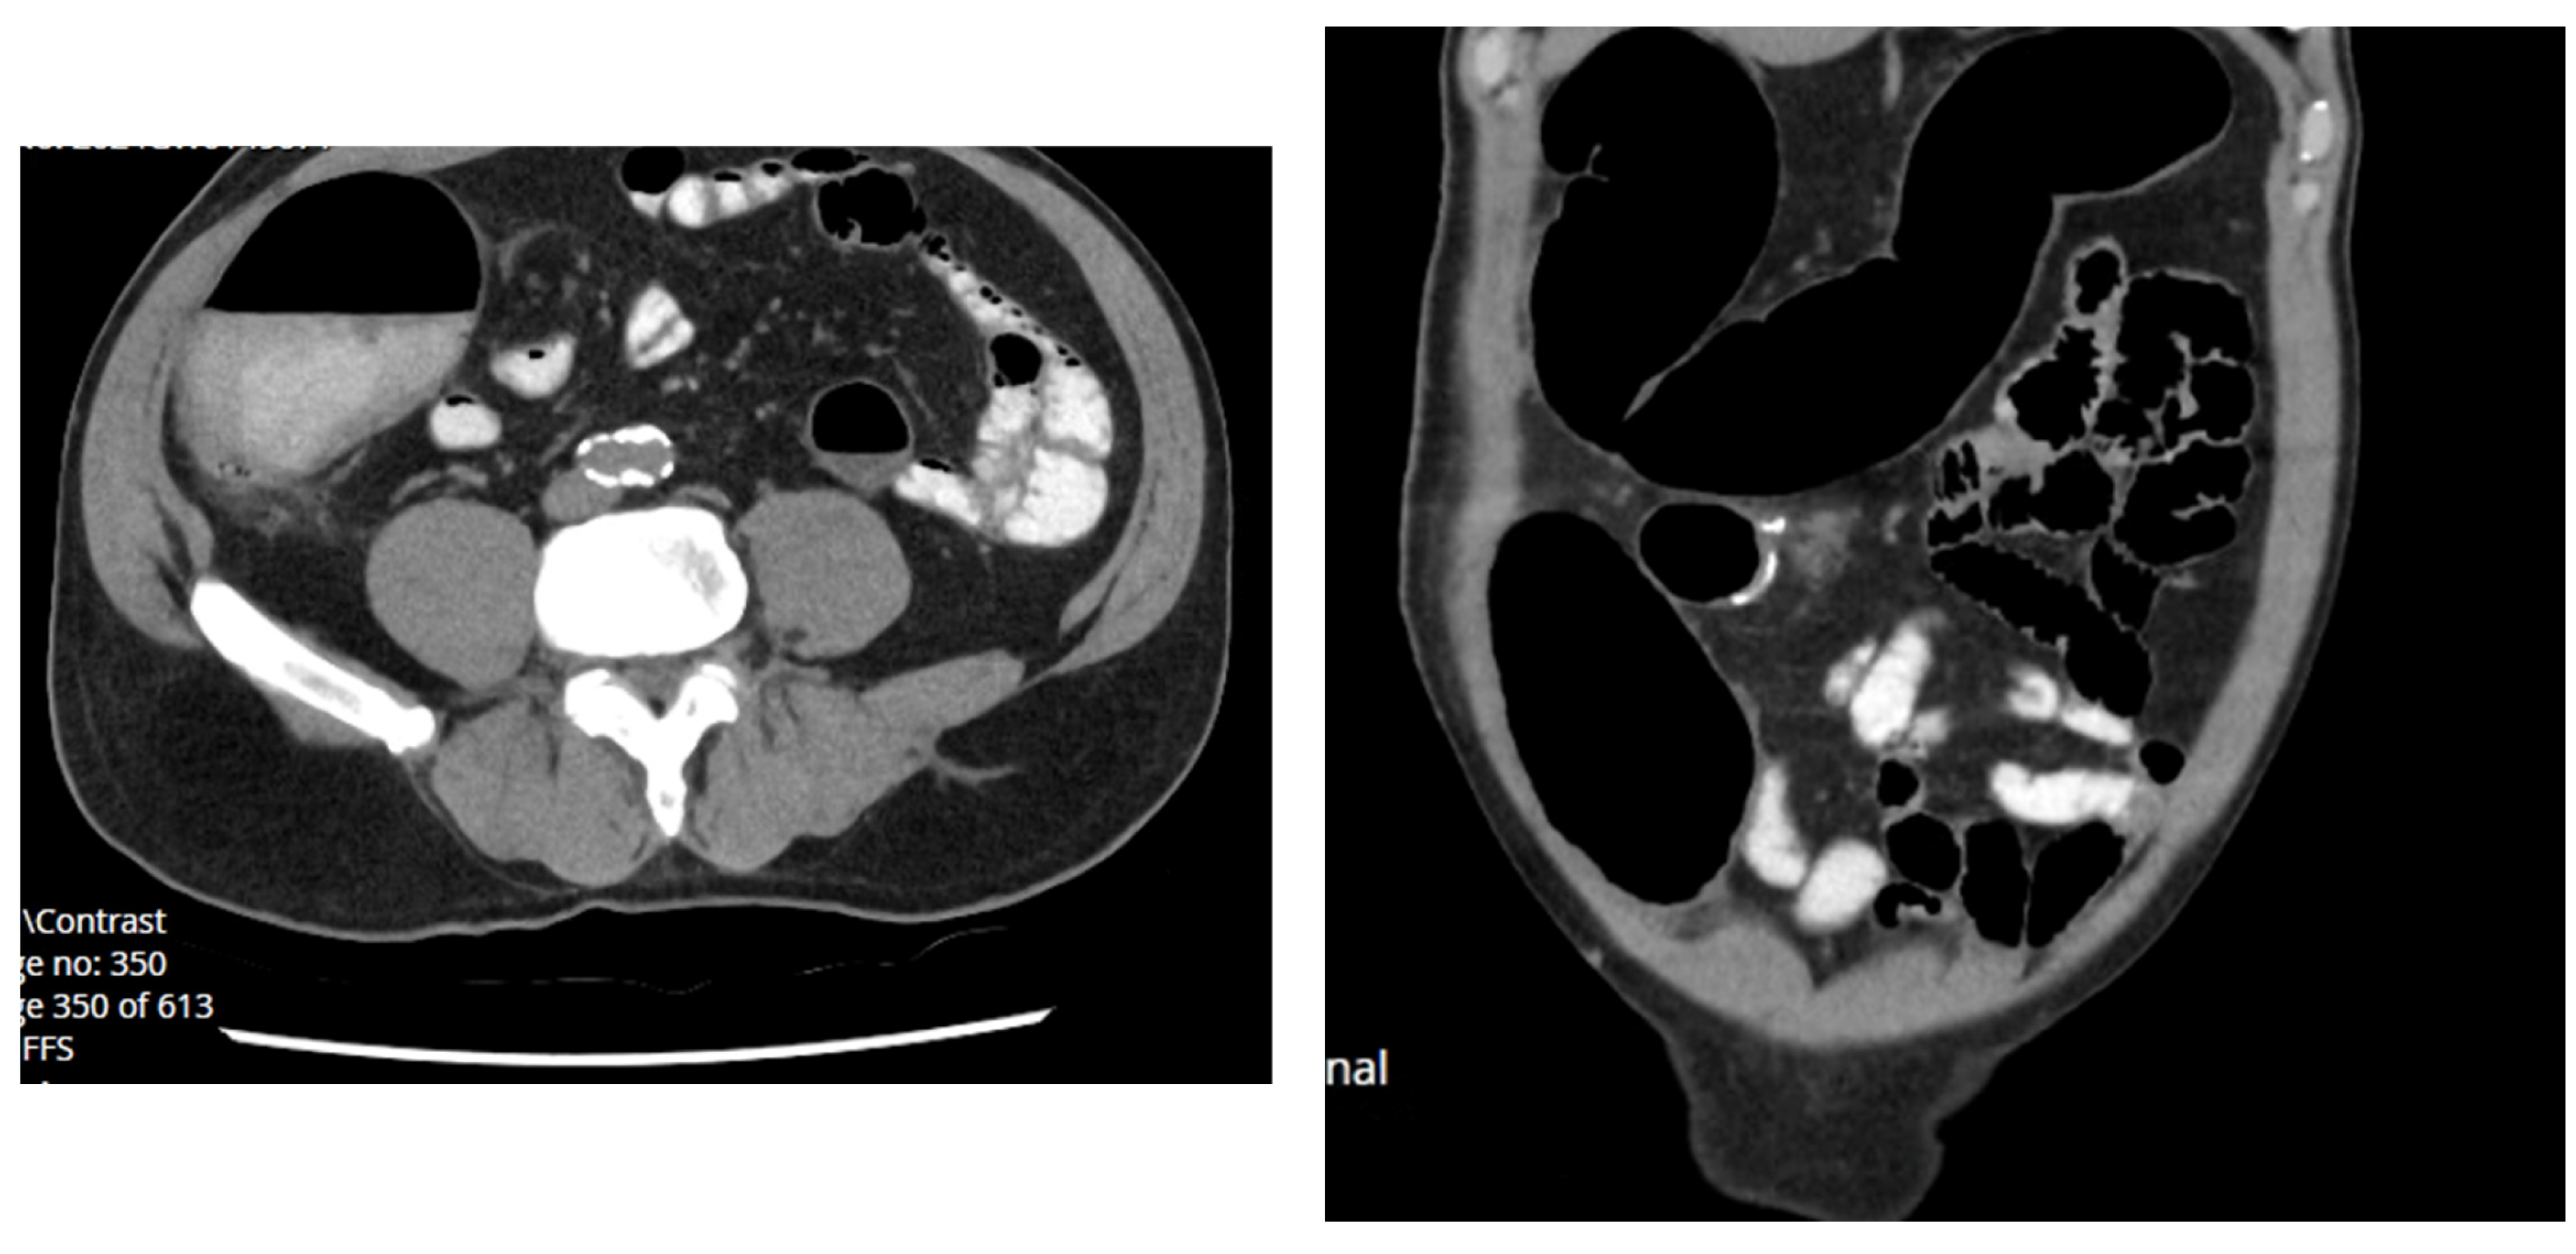

2.1.1. Case 1

2.1.2. Case 2